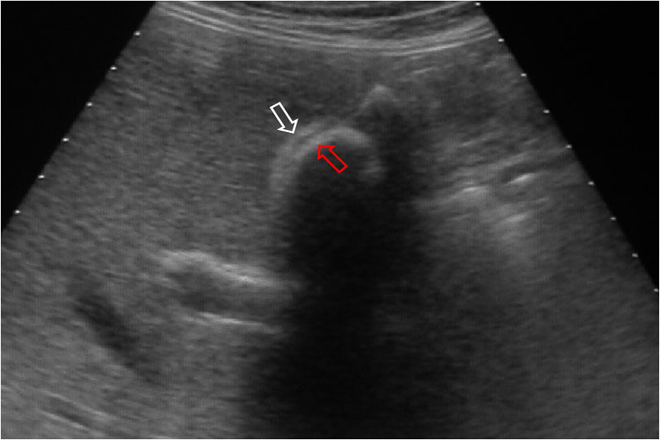

La ecografía abdominal constituye el examen inicial en la patología vesicular, por sencillez, reproductibilidad y bajo costo.

Todos los pacientes fueron estudiados con ecografía abdominal, al menos siete días antes de la cirugía, por un radiólogo experto, evaluándose parámetros como presencia o ausencia de  lumen, número y tamaño de los cálculos y grosor de la pared vesicular.

Tipo I: lumen visible, pared delgada, cálculos visibles.

Tipo II: vesícula distendida, lumen visible, cálculos visibles y pared engrosada > de 3 mm.

Tipo III: lumen no visible, pared de grosor indeterminado, uno o más cálculos con sombra acústica.